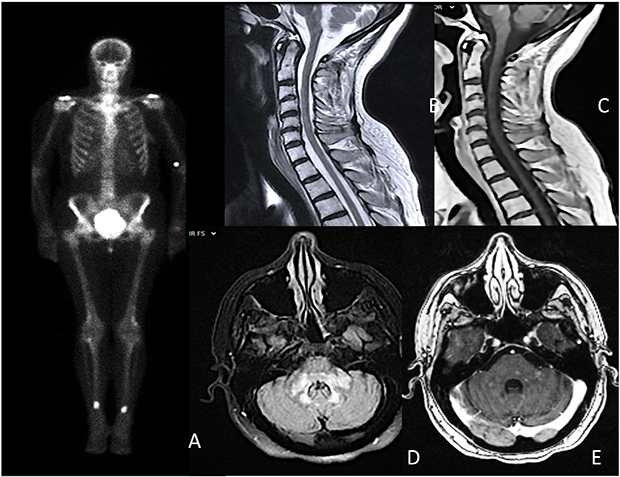

Foto: Archivo